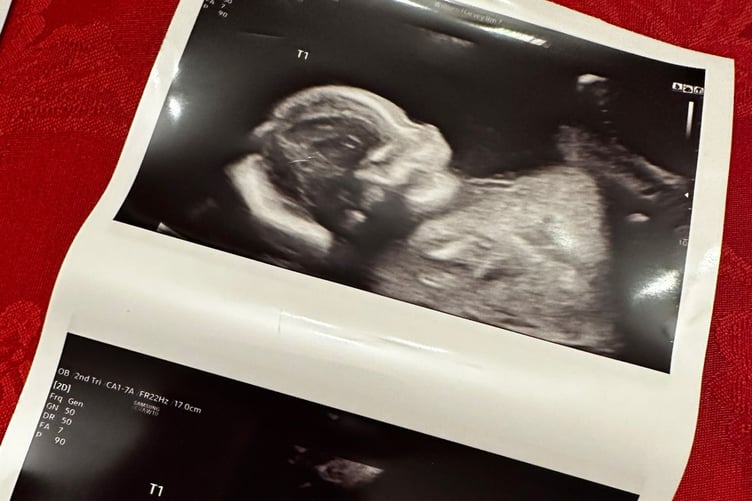

The couple say twins do run in the family but they were not expecting the news at their six-week scan.

Lauren said: "They could see two and needed to do an internal scan. They did the internal scan and could see viable babies.

"Hannah's face dropped. We're very excited."

The triplets are due in June but Lauren will have a scheduled c-section at around 34 weeks as it is a high risk pregnancy.